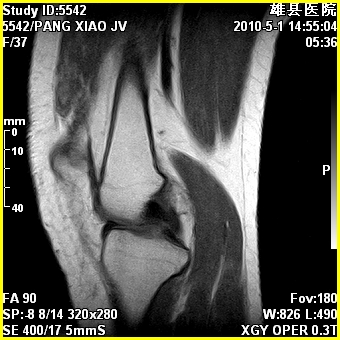

标题: MRI2894:患者右膝关节疼痛两月余,无明显外伤史 [打印本页]

标题: MRI2894:患者右膝关节疼痛两月余,无明显外伤史

右股骨下端前内侧类圆形异常信号,位于干骺端,呈长t1长t2改变,但信号不均,t1图上病灶中心见小片状稍高信号影,t2图上见散在稍低信号影,stir像呈高信号,因病灶较小,缺乏特征性改变,结合患者年龄及部位,考虑嗜酸性肉芽肿可能性大。胫骨关节面下的小囊状异常信号,如果一元论考虑则为嗜酸性肉芽肿,不过发生在这个部位的少见,二元论考虑为邻关节骨囊肿。半月板与前后交叉韧带均未见异常。

右股骨下端前内侧干骺端囊性良性病变,考虑 1内生软骨瘤 2骨囊肿 3肉芽肿。